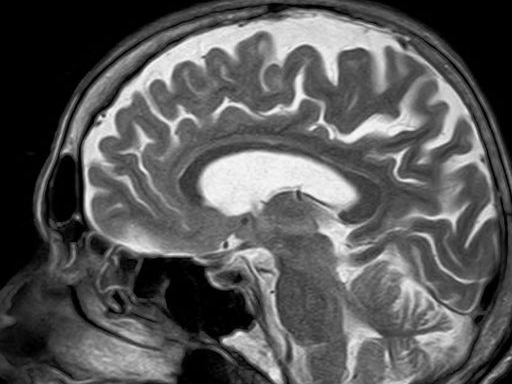

The data in imaging starts with generation of a medical image usually depicting the inside of a body. The image is derived from either a shadow in X-rays or measuring time gap between two photons in Nuclear Medicine or echoes from sound waves in Ultrasound or a radio signal from Hydrogen molecules excited by a magnetic field in an MRI system. These signals, when converted into pixels, combine to give us an image of the body or organ being studied. Highly trained Radiologists then interpret the image to locate or confirm a condition like a broken bone or tumor. This leads to a diagnosis to guide appropriate treatment or further monitoring as the case may be.

As imaging capability increases to measure smaller signals or compute more data to derive usable information, the clarity and depth of the scan improves. The radiologists look for comparisons between a known healthy or diseased anatomy and what is presented to them.

The diagnosis is derived from current data sets being compared to historical records. What makes it complex is the uniqueness of human anatomy. A human heart or brain is so similar yet so unique for each person that you cannot easily program a computer to look for condition X in location Y. That was the case until now, enter machine learning and artificial intelligence which may make automated imaging diagnosis possible.